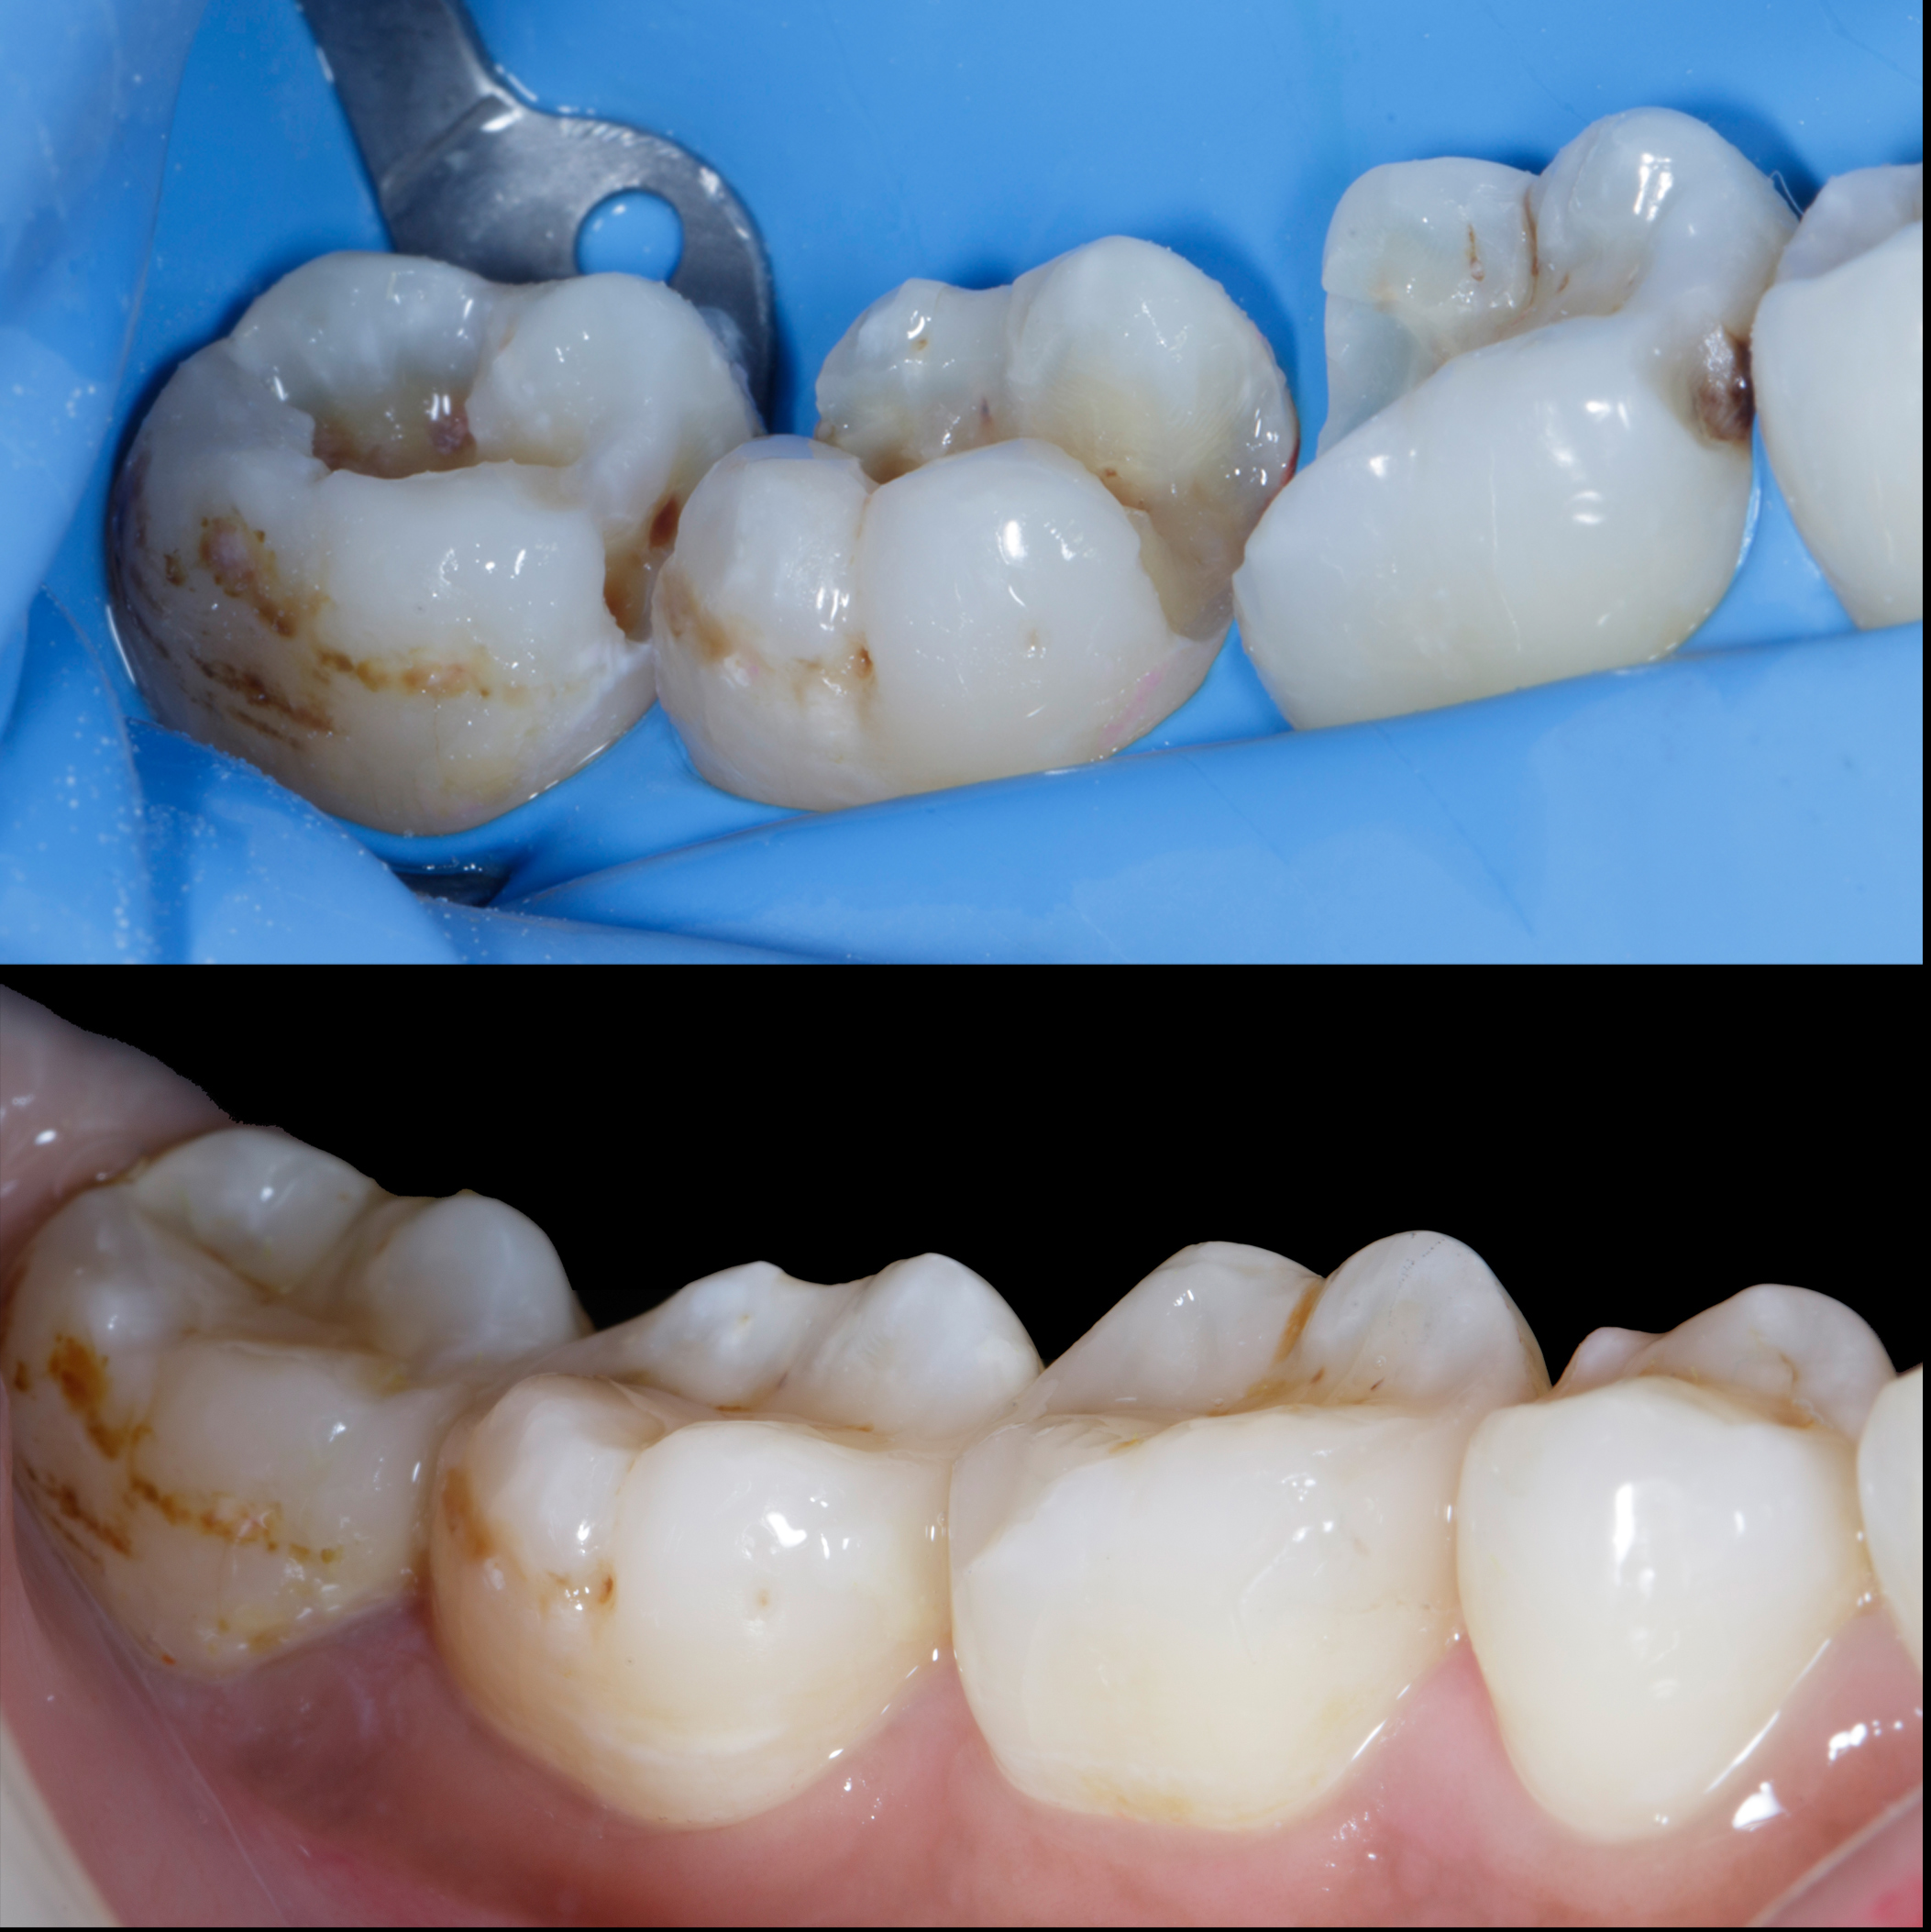

Figure 12

Figure 13

Figure 12. Post op after 15 days.Figure 13. Buccal view, Post of after 15 days shows healthy gums with papilla filled with ideal contacts and contours.

Figure 14

Figure 14. Before and after showing close to natural contacts / contours.

Figure 15

Figure 15. Showcasing extent large defect restored back to its natural form and function.

Figure 16

Figure 16. Buccal view - Showcasing extent large defect restored back to its natural form and function.